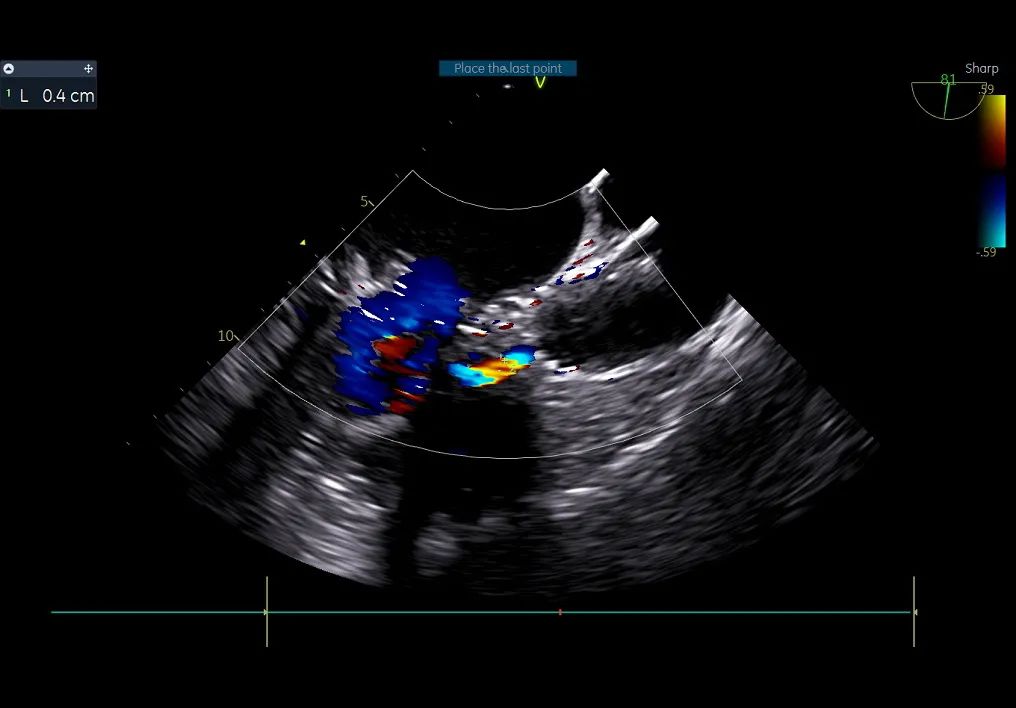

瓣周漏

术中导丝跨瓣后20mm球囊预扩,超声判断冠脉风险尚可,植入L23 VenusA Plus可回收瓣膜位置良好,用23mm球囊后扩支架下缘,微少量瓣周漏。

术后即刻血压135/65mmHg,狭窄解除,释放后超声测量瓣下支架长度6mm标准位释放瓣膜位置完美。整台手术用时不足1.5小时,麻醉、超声等团队全程协作为手术顺利完成保驾护航。